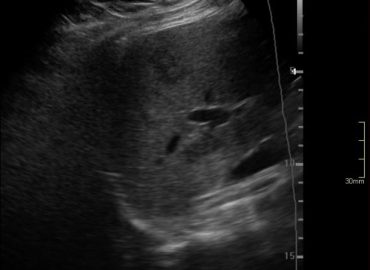

Paciente masculino de 30 años de edad, con dolor abdominal y hematuria.